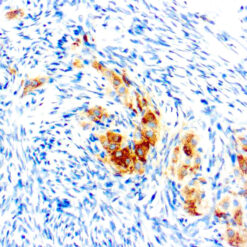

This antibody reacts with a 33-36 kDa protein known as ERCC1 (excision repair cross complementing) polypeptide. ERCC1 is required for nucleotide excision repair of damaged DNA and is homologous to RAD10. In mammalian cells, XPG cleaves 3’ of the DNA lesion while ERCC1-XPF complex makes the 5’ incision.

| Cellular Localization | Nuclear |

| Detection System | PolyVue Plus – Two Step Detection System or Montage PolyVue Plus Auto Detection System for Montage 360 System |